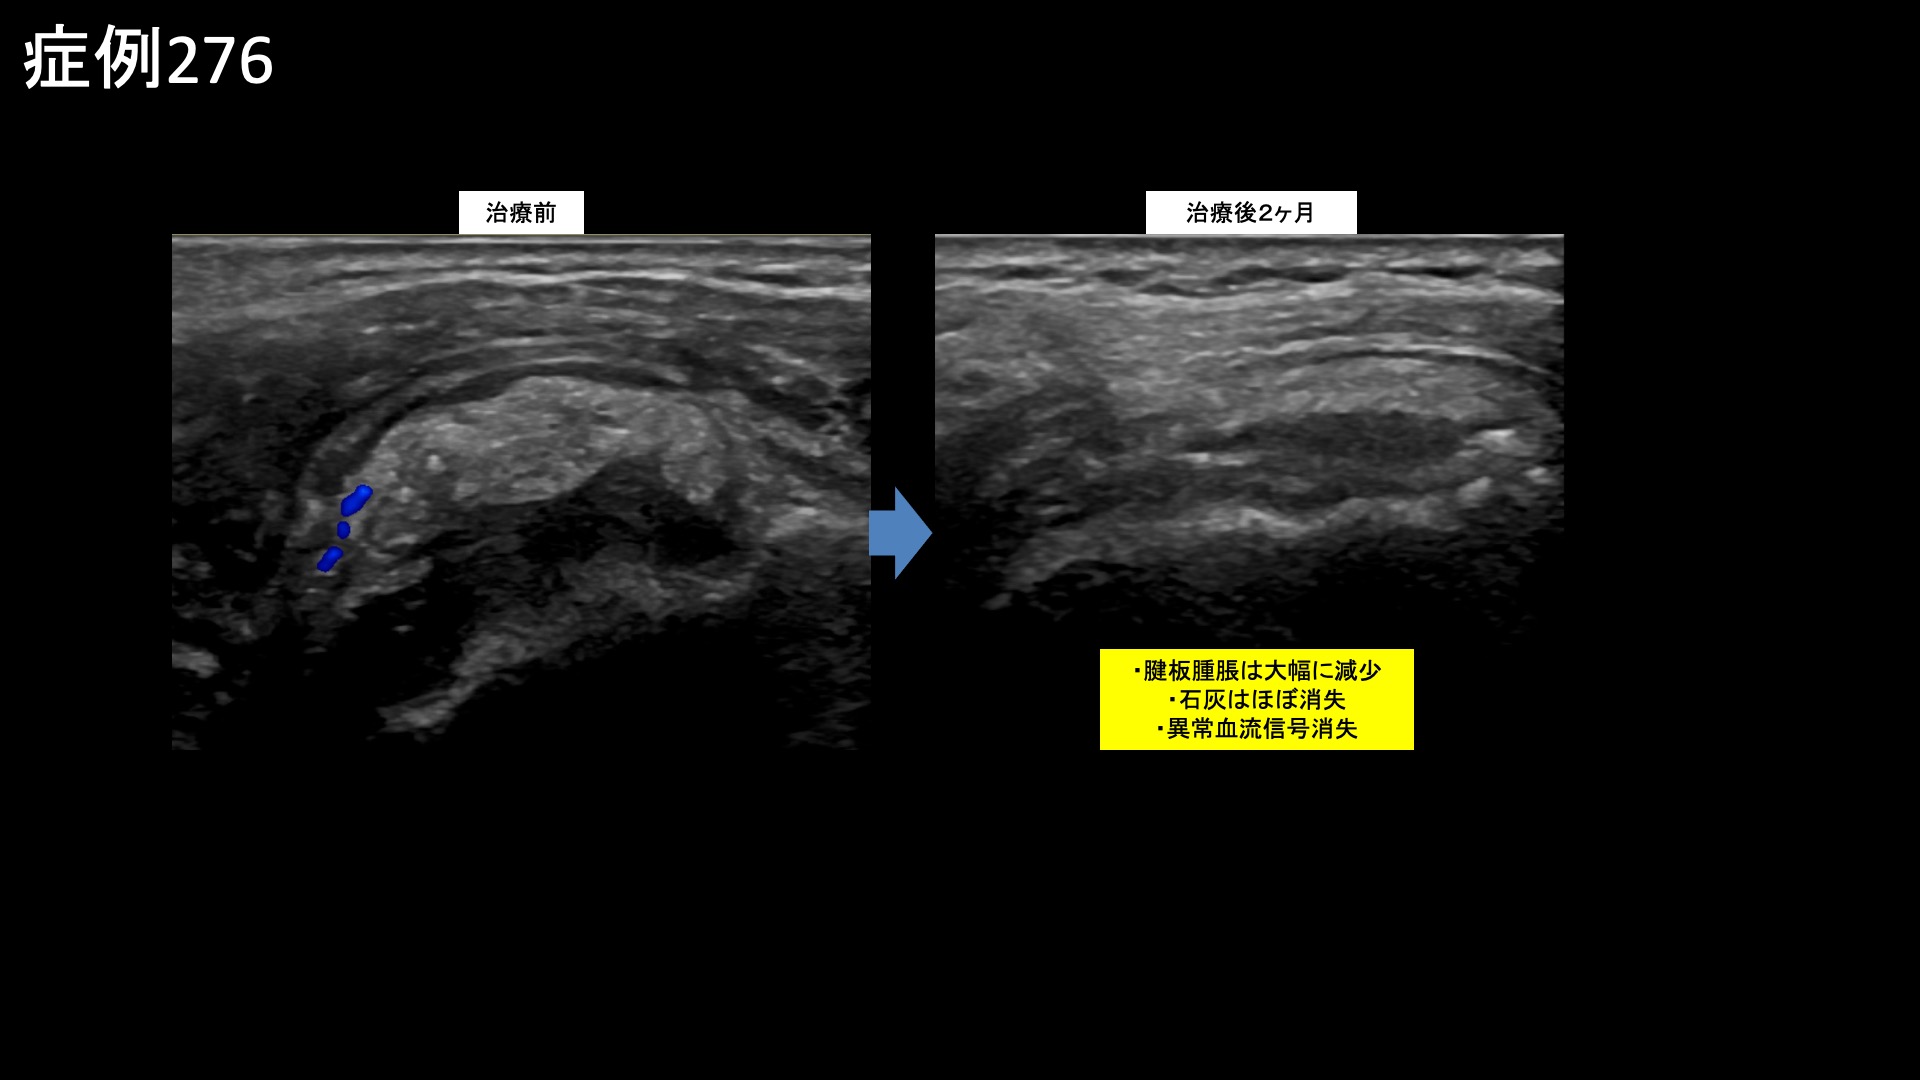

治療後2週間くらいから改善し、治療後3週間では痛みがだいぶ取れて、腕を水平までは上げられるようになりました。首のツッパリが無くなりました。さらに改善が進み、治療後1ヶ月半を過ぎてくると、ほとんど日常生活に支障が無くなりました。治療後2ヶ月、可動域は外転160度、外旋60度、反対の肩に手を回すなどの水平内旋動作も回復し、後方の結帯動作では第4腰椎レベルまで腕を後ろ手に回せるようになりました。回復の速さに周囲からも驚かれたそうです。エコー検査をすると、石灰はほぼ消失、腱板の腫脹も大幅に減少して周囲の(炎症を反映した)異常血流信号も消失していました。画像上も劇的に改善しました。非常に経過良好でしたので、特段の注射加療を行うこともなく治療後3ヶ月の再診としました。その再診時、痛みはほぼ消失していました。首の張りも無くなり、一緒に治療を受けて良かったと言われました。この時点で終診となりました。

粗大な石灰沈着がどのタイミングで起きたかは不明ですが、比較的新鮮なものであったことは間違いありません。こうした場合、微細動脈塞栓術(運動器カテーテル治療)により炎症を強力に鎮めると、完全に石灰が吸収されることをよく経験します。本症例でも典型的な良好な経過を辿りました。石灰が残っても痛みがおさまった後は特に支障がないことが多いですが、中には残存した石灰が動作に伴うインピンジメント(肩関節内の衝突)を起こして新たな損傷/炎症を惹起することがありますので、無いに越したことはありません。石灰を指摘された場合は、あまり長く放置せずに早めにカテーテル治療を検討されることをおすすめします。